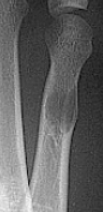

| What do the arrows show? | Stress fracture |

| Describe what has happened at the shaft of the 3rd met | Exuberant periosteal new bone production. May have resulted if a stress fracture was not treated and the patient continued weight bearing activities. |